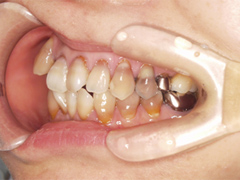

写真(1)完成後の写真

大きな虫歯で神経の治療が必要になった

治療について

- 治療内容/左上4番目歯1本.根の治療、土台(心棒)ファイバーコアと被せ物を審美セラミッククラウン

- 費用/土台(心棒)1本あたり2万円,上部被せ物1本あたり15万円,審美専門歯科技工士立会い色合わせ3万円,合計20万円(税別)

- リスク・副作用/神経治療後に痛みがでることがあります。

- 期間/1カ月